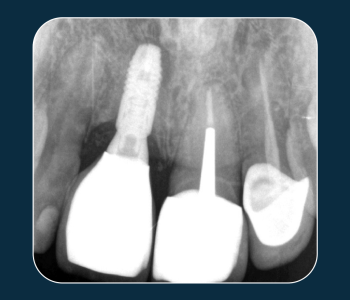

Este caso clínico demuestra los conceptos básicos de la técnica BioBulk Fill para la protección pulpar indirecta, utilizando el material Biodentine™ XP como sustituto de…

Descubre cómo el Dr. Renner aprovecha las propiedades mecánicas únicas de Biodentine™ para usarlo como material de núcleo permanente en la colocación de una corona…